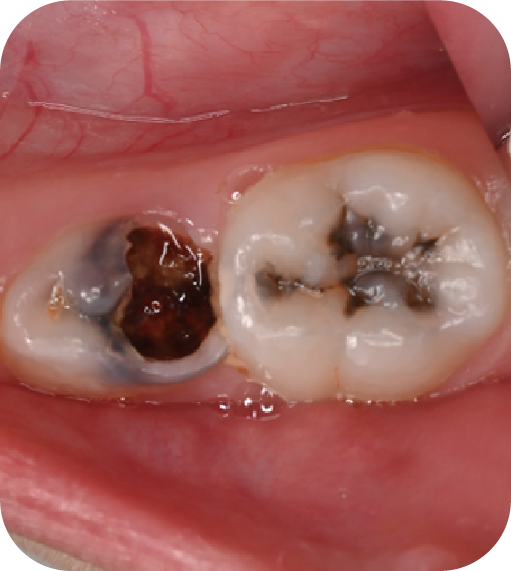

為什么要做窩溝封閉?

后磨牙,也就是大牙咬合面上凹凸不平的裂隙,這就是“窩溝”。窩溝有很多形狀,有的是狹長的裂隙形狀,還有的在牙齒深處又會分成幾條小溝。這些地方用牙刷很難深入清潔,于是就成了衛(wèi)生死角,細菌特別喜歡在里面生存,不斷產(chǎn)酸腐蝕牙齒,蛀牙就這樣產(chǎn)生了。如果我們用窩溝封閉把這些衛(wèi)生死角封起來,那既可以杜絕食物和細菌進入窩溝內(nèi),也可以讓窩溝處的清潔變得更簡單,這就是做窩溝封閉的目的。同時它也是世界衛(wèi)生組織、國家衛(wèi)健委都推薦的防齲方法。